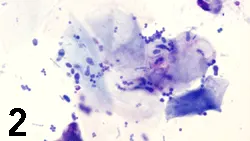

Smear from right ear canal. (modified Wright’s stain; original magnification, 100×)

Cytologic Evaluation. The smear from the left ear canal (Figure 1) contained large numbers of squamous epithelial cells and markedly increased numbers of broad-based budding yeasts. The findings were consistent with an overgrowth of Malassezia pachydermatis. The smear from the right ear canal (Figure 2) contained squamous epithelial cells, scattered neutrophils, large numbers of bacteria (cocci, fewer rods), and fewer Malassezia organisms. The findings were consistent with neutro­philic inflammation with a mixed infection.